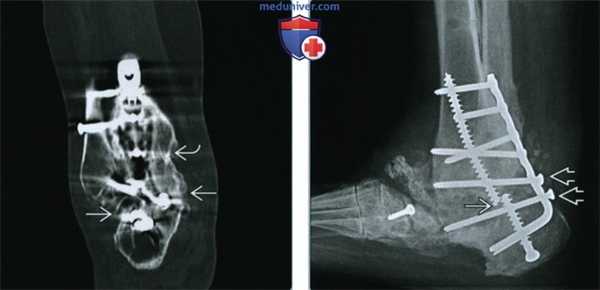

а) Терминология:

1. Синоним:

• Сращение голеностопного сустава

2. Определение:

• Хирургическое соединение большеберцово-таранного сустава ортопедическими металлоконструкциями для достижения костного сращения

1. Общая характеристика:

• Лучший диагностический критерий:

о Мостовидные трабекулы через полость сустава

(Слева) Рентгенография в боковой проекции: шесть месяцев спустя после артродеза голеностопного и таранно-пяточного суставов с клинковой пластиной наблюдается появление трабекул, соединяющих большеберцово-таранный и таранно-пяточный суставы. Тем не менее, при рентгенографии возможна переоценка костного сращения вследствие наклона луча или наложения различных частей сустава.

(Справа) КТ кости, сагиттальный срез, реформация (выполнена по причине постоянного болевого синдрома), этот же пациент: визуализируется сращение в большеберцово-таранном суставе, но не в таранно-пяточном.

2. Рентгенография артродеза голеностопного сустава:

• Нормальные находки после артродеза:

о Ранние послеоперационные находки:

- Некоторые хирурги выполняют остеотомию малоберцовой кости и соединение медиальной части ее кортикального слоя с большеберцовой костью для создания каркаса поперек полости сустава («инкорпорация малоберцовой кости»)

- Близкое сопоставление суставных поверхностей

- Неинкорпорированный костный трансплантат

о 2-6 месяцев после оперативного лечения:

- Мостовидные трабекулы через полость сустава:

Первоначально может вовлекаться небольшая часть сустава («точечная сварка»)

Если одна часть сустава срастается, оставшаяся также имеет тенденцию к сращению через некоторое время

- Сращение костного трансплантата; вероятно наличие некоторой резорбции

о Трудности в диагностике:

- Косой луч при рентгенографии может привести к плохой визуализации краев сустава

- Наложение кости, не относящейся к суставу, также может затенять края сустава

- Любая проблема может привести к ошибочному диагнозу успешного сращения

• Нарушение функции артродеза:

о Постоянная визуализация суставного пространства:

- КТ является более точным методом, чем рентгенография, если суставное пространство сохраняется открытым

о Просветление, окружающее фиксирующие винты или пластины:

- Минимальное просветление является нормой и может стабилизироваться

- >1-2 мм может влиять на подвижность

о Перелом металлоконструкции

о Миграция металлоконструкции

о Изменения в расположении сустава

о Периостальная реакция:

- Может привести к избыточной подвижности или инфекции

3. КТ артродеза голеностопного сустава:

• Те же признаки, что и при рентгенографии, но более четкая и ясная визуализация

• При наличии у пациента болевого синдрома после артродеза на КТ может визуализироваться нарушение сращения сустава, которое не видно на рентгенограмме

• Возможны ложно-положительные диагнозы сращения, если суставное пространство искривлено в плоскости сканирования:

о Следует внимательно оценивать сагиттальные и фронтальные реформации для точного различения между артефактом частичного объема и настоящим сращением

4. МРТ артродеза голеностопного сустава:

• Костный мозг и трабекулы в полости сустава

• Ограничение вследствие артефактов от металла

5. Рекомендации по визуализации:

• Лучший метод визуализации:

о КТ; часто полезно ↑ кВп

• Протокол исследования:

о Необходима фронтальная и сагиттальная реформация

(Слева) КТ кости, сагиттальный срез, реформация, этот же пациент: подтверждается наличие сращения в большеберцово-таранном суставе и отсутствие сращения в таранно-пяточном. Важно подтверждать данные во фронтальной реформации и сагиттальном срезе, чтобы избежать ошибки в диагнозе из-за артефакта частичною объема.

(Справа) Рентгенография в боковой проекции после сращения голеностопного и таранно-пяточною суставов: перелом фиксирующего винта В, указывающий на продолжающееся смещение. Два фиксирующих винта отклонены назад и их головки выступают. В средней части стопы визуализируется артропатия Шарко.